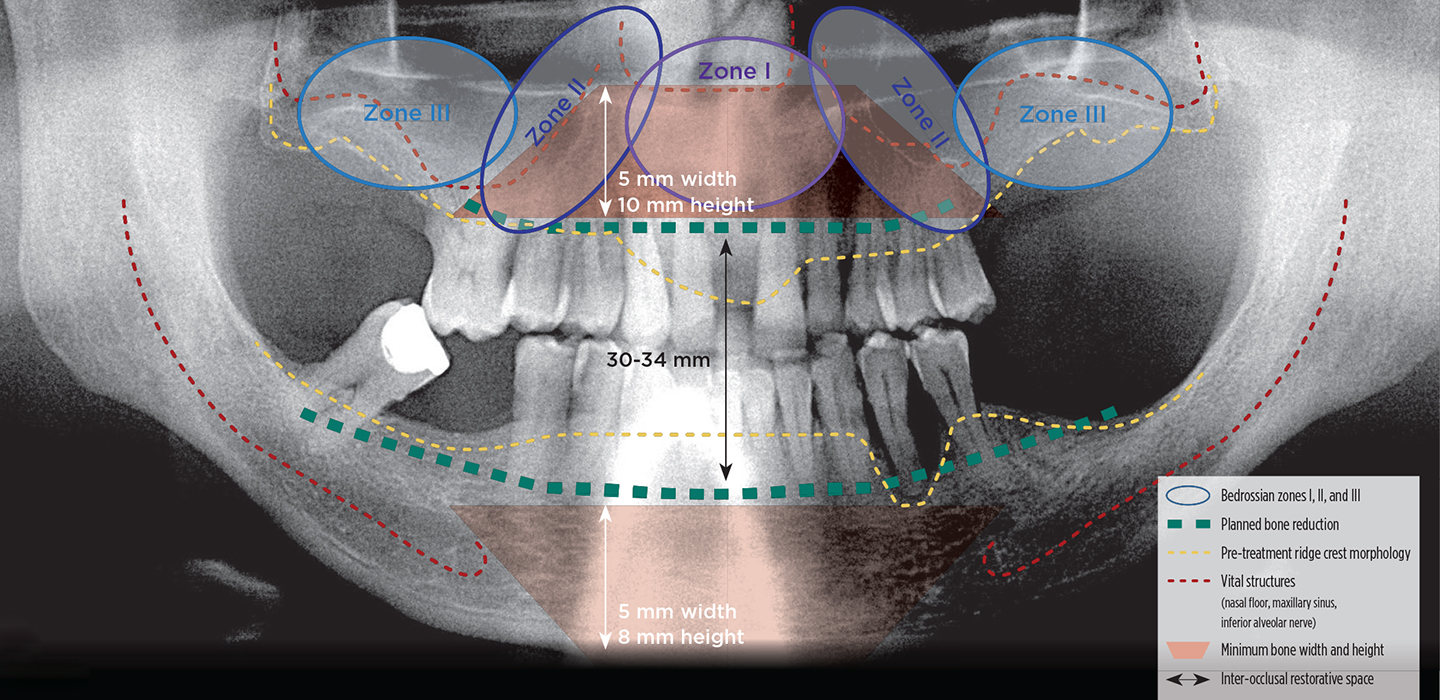

Radiographic Diagnosis and Treatment Planning Survey

• Presence of adequate bone in Bedrossian zones I (pre-maxilla) and II (bicuspid region)

• Location of vital structures, mental nerve, and maxillary sinus

• Presence of composite ridge defects (ridge defect with missing hard and soft tissues)

• Inter-arch space measured between maxillary and mandibular ridge crests at patient’s VDO

• Estimated need for bone reduction to create required inter-occlusal restorative space

• Alveolar ridge width ≥ 5 mm and height ≥ 8 mm in the anterior mandible

• Alveolar ridge width ≥ 5 mm and height ≥ 10 mm in the anterior maxilla

• Bone density classification at primary and backup implant sites

• Verify adequate medullary bone volume for biologic integration at implant sites

• Absence of sinus pathology and patent osteomeatal complex

Diagnostically Driven Treatment Planning

Once the surgeon and the restorative dentist have consulted with the patient and performed a pre-treatment patient evaluation, interdisciplinary treatment planning to identify treatment options for the patient’s dental rehabilitation is completed. The surgeon should have completed and documented a dentofacial and intraoral patient evaluation as well as a radiographic diagnosis and treatment planning survey using cone beam computed tomography (CBCT) (Figure 1) to explore possible treatment options from a surgical perspective. After review of this information, the restorative dentist performs model-based diagnosis and treatment planning. The clinicians jointly review the surgical and restorative treatment planning information and select the treatment option that can be strongly recommended, as well as viable alternatives, for patient education and case presentation.

Fig 1. Radiographic diagnosis and treatment planning survey.